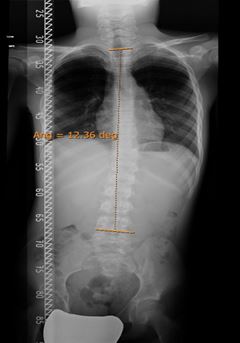

Hábito asténico. Escoliosis.